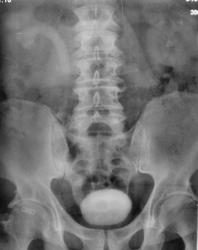

Признавайтесь, куда делась средняя треть правого мочеточника? Ее как-будто ножом отрезали под линейку, а ниже-сплошное безобразие! "ЧТО" может как обезобразить орган-банальная МКБ с частичной обтурацией просвета или опухоль? А в пузыре тоже камни?

Вы правы, камней не много, их - до "фига"...

А деформация мочевого пузыря никого не смущает?

Отчего же не смущает?))) смущает...она и есть первопричиной образования ТАКОГО камня в мочеточнике, теперь об этом можно сказать с уверенностью, ее генез - выраженое увеличение размеров простаты.

С простатой при отсутствии УЗИ достаточно пальцевого осмотра хирургом до экскреторного исследования. Если простата не увеличена пальпаторно, то получив такую картинку мочевого пузыря на первых минутах после введения контраста, я бы сделал косые снимки мочевого пузыря (заодно и тень в н/3 правого мочеточника покрутить).